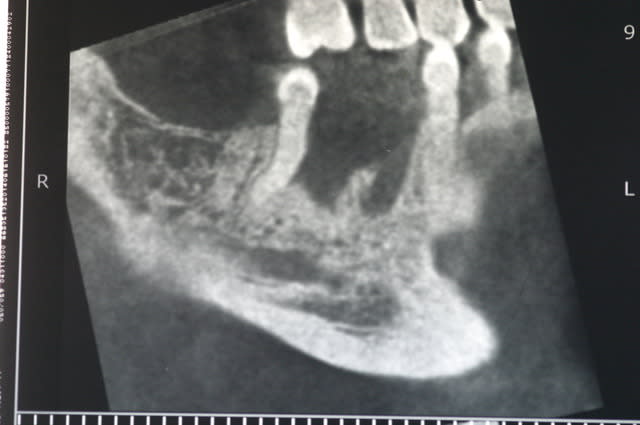

ci joint les photos des coupes scanner d'un patient à qui j'ai proposé de poser un implant afin de remplacer la 36. sur les coupes, on vois nettement le dédoublement du NAI.

Après discussion avec le radiologue qui ni avait pas fait allusion dans son compte rendu, celui-ci me dit que le canal le canal ne contient que quelques filet nerveux (je ne sais pas comment il peut voir cela..) et que je peux passer au travers sans problèmes.

tient pour revenir sur ce que disait Pxav, sur une image comme celle ci, vous passeriez en vestibulaire? c'est vrai qu'il y a de la place, mais je n'ai pas osé...

moi je tenterais pas non plus ce cas là, tout simplement parce que même si tu peux le mettre en vestbulaire, tu n'es plus du tout dans l'axe de la prothese. Alors peut être qu'on peut rattraper avec des pilliers adaptés( et encore), mais à long terme qu'est ce que ça va donner.